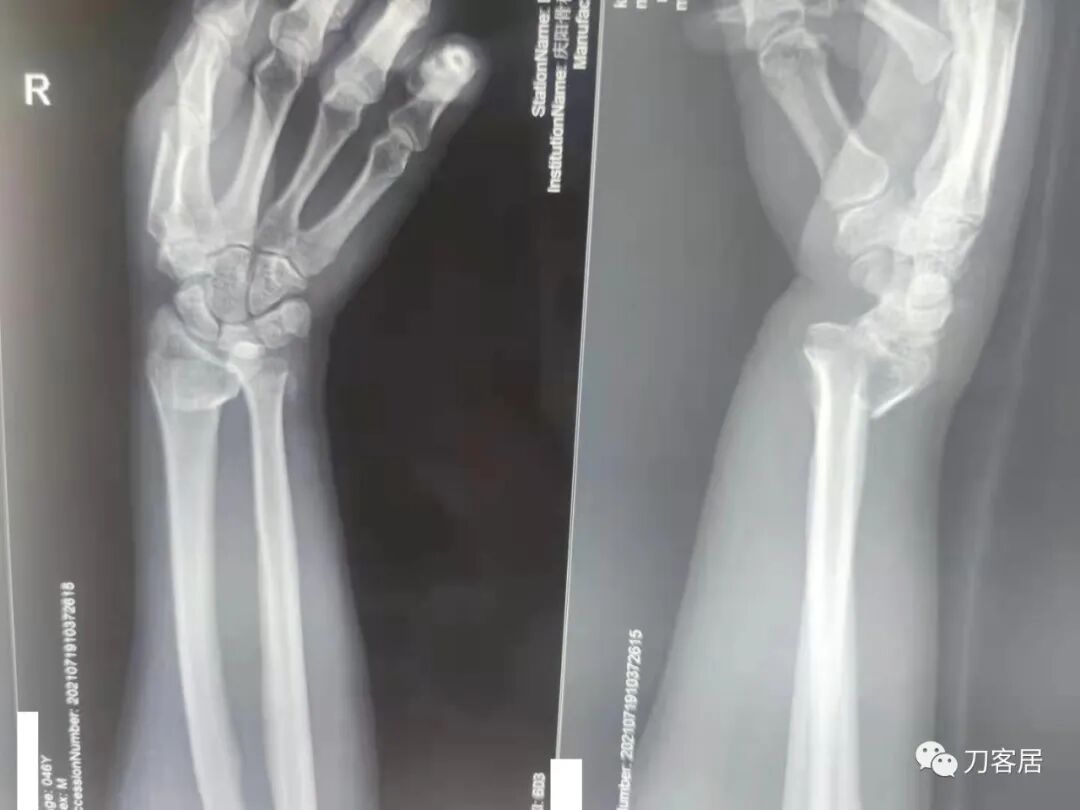

下面是这个6岁孩子,尺桡骨远端双骨折的术前及术后片子和外观照片。

1.  这是一个很简单的6岁儿童无移位的尺桡骨远端骨折。没有皮肤损伤,没有移位,没有骨折碎块儿。

2.  这个骨折处理起来也很简单,单纯的打石膏托或者中医的小夹板,或者正规的包括腕关节和肘关节的管型石膏外固定4周即可治愈该骨折。实在不行,如果这个孩子比较听话,不太调皮的话,用一本书,一个三角巾悬吊固定4周,都可以治愈该骨折。但是给这个患者用外固定架做了手术,而且桡骨远端的几颗克氏针距离骨折线太近,其中一枚克氏针进入到骨折间隙内。从这个术中图片来看,术者的外固定手术技术也有待于进一步的提高。毕竟术者应该还很年轻。从X线片来看,前臂及手的尺侧有不透光影,应该还使用了外固定石膏绷带托,而且我猜测应该是高分子的石膏绷带托,这个是纯属猜测,不一定是对的,不过如何解释前臂尺侧的不透光影呢?如果真是用了石膏绷带外固定的话,那为啥要做手术呢?外固定架术后就不该再用石膏绷带托辅助了。

这个病例,6岁的孩子,尺桡骨骨折在同一个平面,且都为小斜行骨折,不是螺旋形,不是粉碎性,不是成角移位性,属于稳定性尺桡骨双骨折,根本就没有任何手术的适应症。